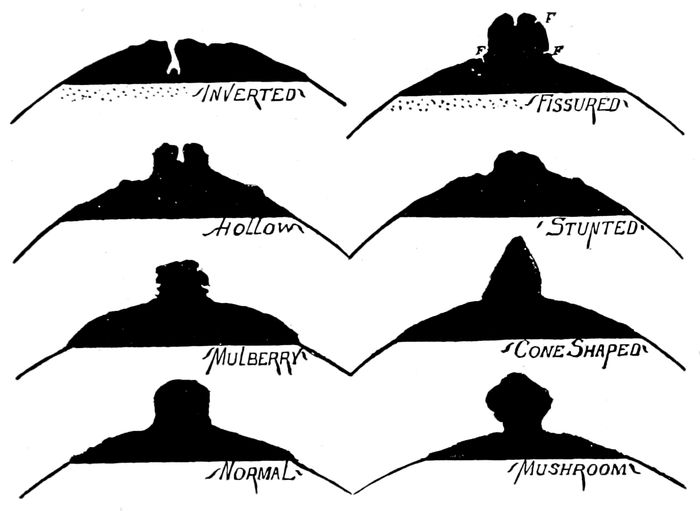

| 108. |

Examples of imperfect nipples |

245 |